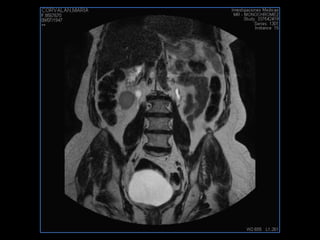

PROTOCOLO abdomen COR T2, AXIAL supresion grasa AX T1 +SAG T2  CON   GADOLINIO :  COR T1+AX T1(DIN) SAT: NO  FASE: RL THK: 6MM  COIL:  GAP: (FACTOR 1.4) 2MM FOV: 40 CM NEX:2 SINCRONIZACION RESPIRATORIA EN 3 O 4 CICLOS ALE

PROTOCOLO pelvis SAG T2, Y FAT SAT (FINOS) AXIAL T1  AX FAT SAT CON   GADOLINIO :  AX T1 Y COR T1 SAT: NO  FASE: RL THK: 3MM  COIL:  GAP: (FACTOR 1.4) 1MM FOV: 40 CM NEX:2 SINCRONIZACION RESPIRATORIA EN 3 O 4 CICLOS ALE